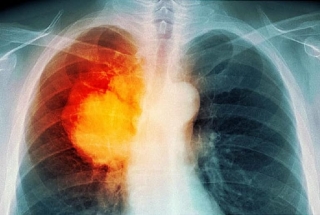

Ung thư phổi là loại ung thư bắt đầu từ các tế bào của phổi. Theo số liệu thống kê năm 2020 của Globocan, ung thư phổi đứng thứ 2 về số ca mắc mới và đứng đầu về số ca tử vong do ung thư ở cả 2 giới trên toàn cầu. Ung thư phổi được chia thành 2 nhóm chính là ung thư phổi tế bào nhỏ (Small cell lung cancer – SCLC) chiếm khoảng 10 – 15% và ung thư phổi không tế bào nhỏ (Non-small cell lung cancer – NSCLC) chiếm khoảng 80 – 85%.

NSCLC lại được chia thành các dưới typ chính là: ung thư biểu mô tuyến, ung thư biểu mô vảy và ung thư biểu mô tế bào lớn. Các dưới typ này xuất phát từ các loại tế bào khác nhau của phổi nhưng được gộp chung một nhóm do chúng có tiên lượng và cách điều trị tương tự nhau.